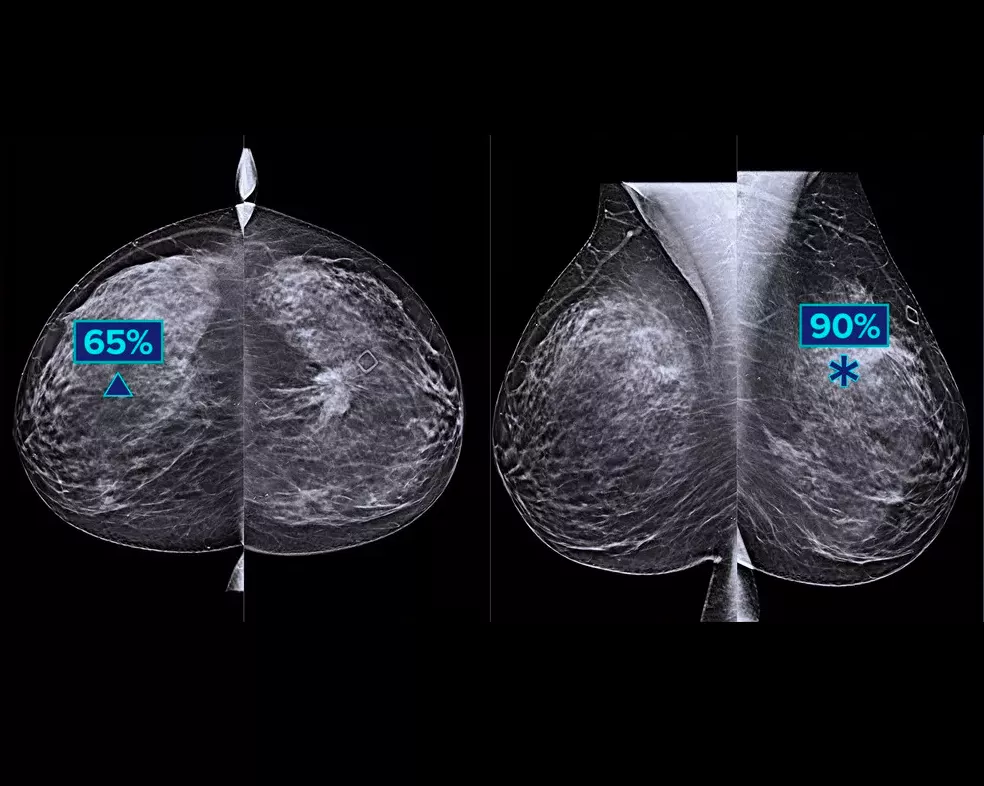

Un algoritmo di deep-learning studiato per coadiuvare le prestazioni diagnostiche dei medici radiologi e individuare i tumori al seno1-3 dalle immagini di tomosintesi ottenute con i sistemi mammografici Dimensions® Hologic. L'algoritmo individua le lesioni probabilmente riconducibili a un tumore della mammella, analizzando ogni sezione della serie di immagini di tomosintesi. Le aree sospette vengono evidenziate sulla stazione di lavoro del medico radiologo per una lettura immediata e un ausilio nell'interpretazione.

Uno studio mostra un miglioramento del 9% della sensibilità di lettura.1.2 Funziona su immagini di tomosintesi standard e ad alta risoluzione, sovrapponendo le informazioni su SmartSlice 3DQuorum e immagini 2D sintetiche.

L'algoritmo cerca 3 gruppi principali di lesioni sospette: calcificazioni, masse, densità con distorsioni e le loro combinazioni. I risultati possono variare in base alla stazione di lavoro usata per la refertazione.

L'integrazione sulla postazione di acquisizione consente di contrassegnare i casi ad alto rischio per una lettura immediata. Le metriche a livello di caso aiutano a classificare i casi per priorità di lettura.

L'unico software basato su deep-learning utilizzabile su una postazione di acquisizione del sistema per mammografia che non necessita di server separato, per una soluzione semplice, pratica e sicura. L'integrazione sulla piattaforma Dimensions offre opportunità di lavoro uniche con strumenti che facilitano la revisione dei casi e l'assegnazione delle priorità.

Hologic ha condotto uno studio su più lettori e più casi (MRMC) per verificare le prestazioni dell'algoritmo Genius AI.3